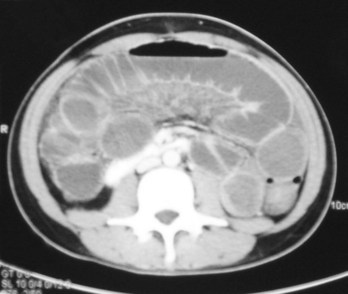

The patient lies on a bed, an X-ray tube passes around the body (Fig. 1.7), and a series of images are obtained. A computer carries out a complex mathematical transformation on the multitude of images to produce the final image (Fig. 1.8).

image

Fig. 1.8 Computed tomography scan of the abdomen at vertebral level LII.

The general principles of computed tomography are described on p. 9. It is important for the student to understand the presentation of images. Most images are acquired in the axial plane and viewed such that the observer looks from below and upward toward the head (from the foot of the bed). By implication:

image the right side of the patient is on the left side of the image; and

image the uppermost border of the image is anterior.

This technique for visualizing CT images applies throughout the whole body. Any changes to this standard are always indicated.

Many patients are given oral and intravenous contrast media to differentiate bowel loops from other abdominal organs and to assess the vascularity of normal anatomical structures. When intravenous contrast is given, the earlier the images are obtained, the greater the likelihood of arterial enhancement. As the time is delayed between injection and image acquisition, a venous phase and an equilibrium phase are also obtained.

The great advantage of CT scanning is the ability to extend and compress the gray scale to visualize the bones, soft tissues, and visceral organs. Altering the window settings and window centering provides the physician with specific information about these structures.